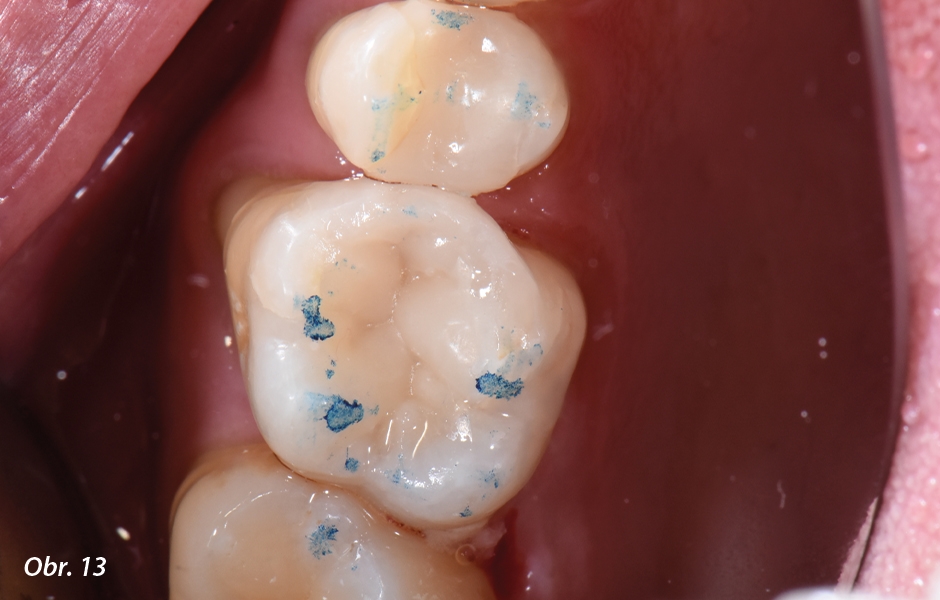

Po kontrole okluze: předčasné kontakty byly odstraněny.

Po vyleštění nástrojem EVE (Comet): pozoruhodně vysokého lesku lze dosáhnout i minimálním leštěním a po rehydrataci oblasti odstín výplně velmi dobře splyne s okolní zubní hmotou.